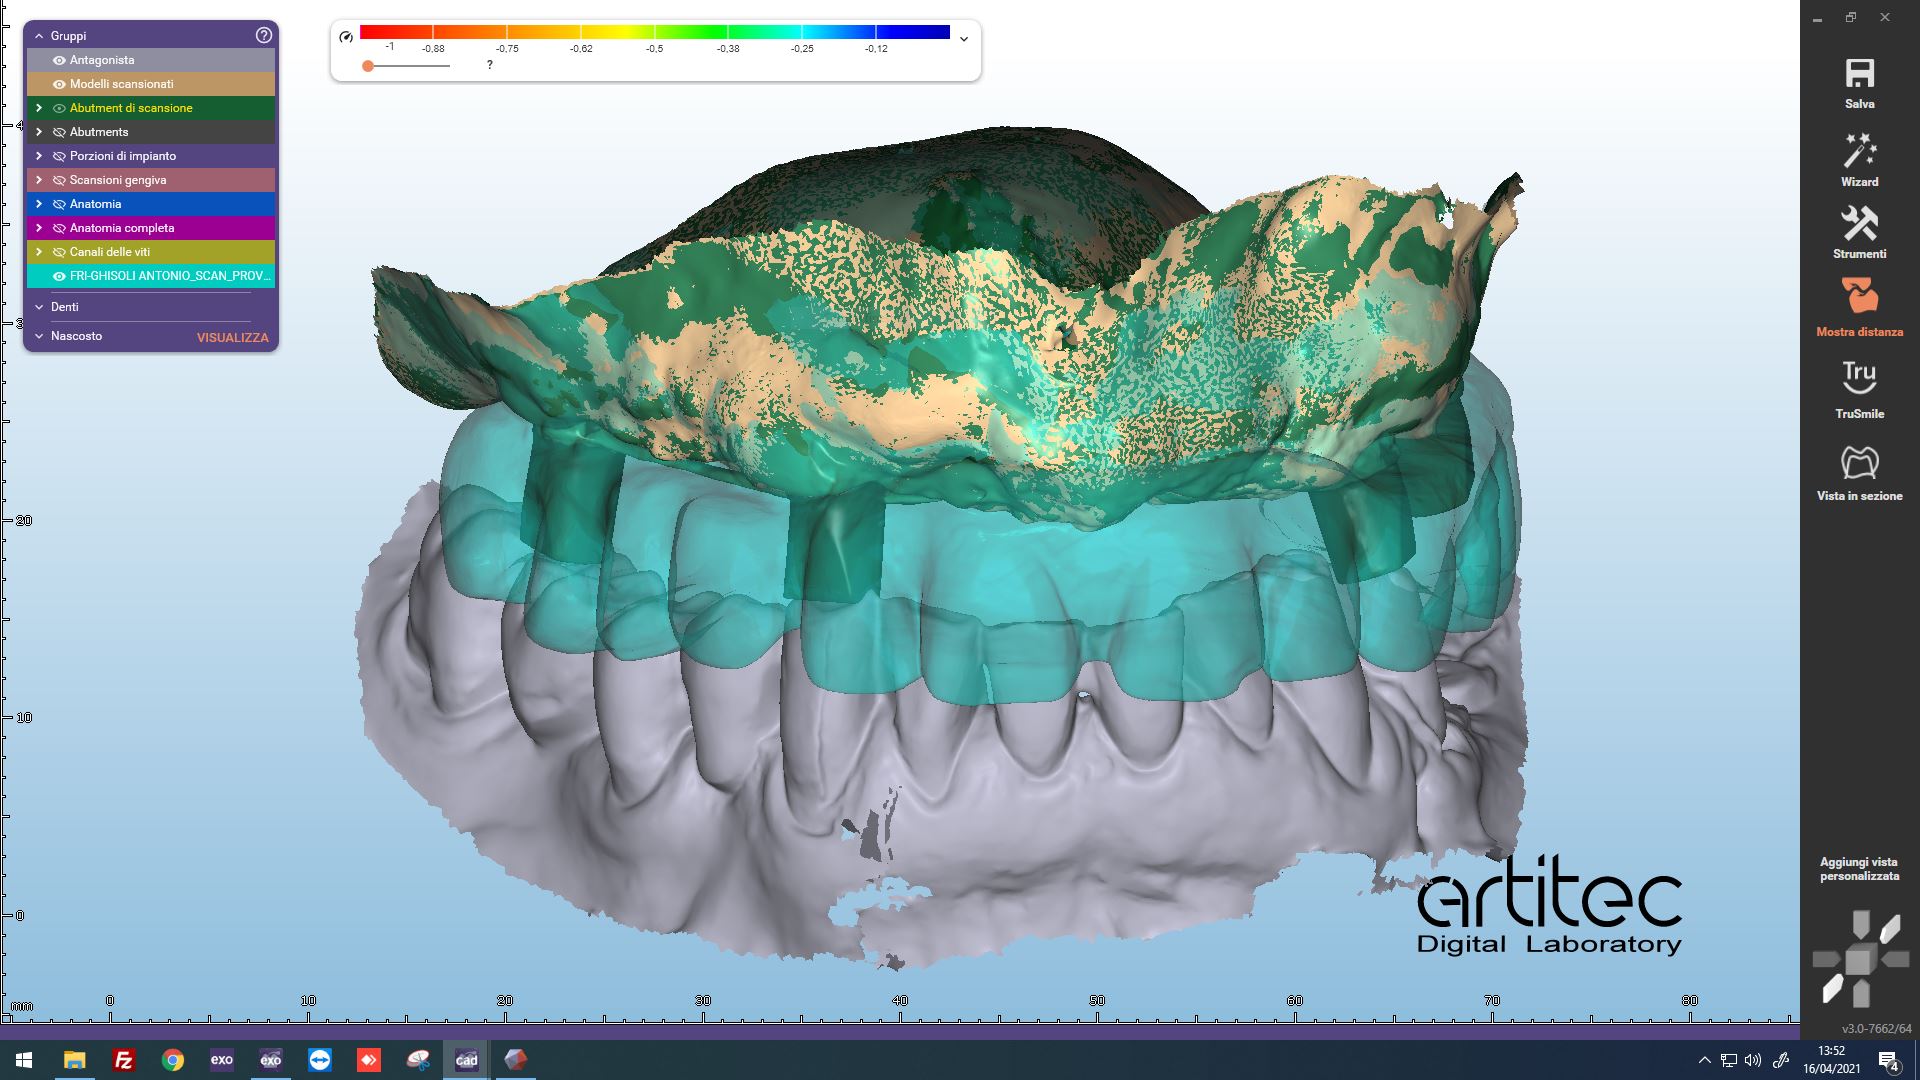

Fig. 2 Ricevimento scansione e match tra scan body e situazione iniziale